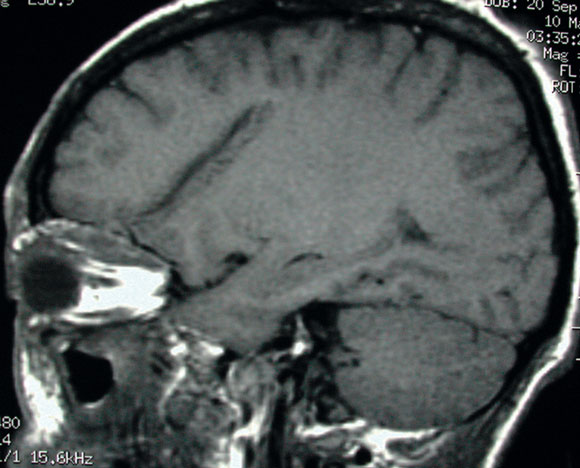

However, as the cerebrospinal fluid appeared normal on microscopy and biochemical examination and showed no growth on culture, the initial diagnosis was questioned. Magnetic resonance imaging of the brain and orbits was performed the day after presentation. This showed a 5 cm tract extending obliquely from the roof of the left orbit into the white matter of the left frontal lobe, associated with a fracture of the orbital plate of the frontal bone (Box 1B). Inflammatory changes, presumed infective, were noted superiorly within the left orbit, resulting in proptosis.

It was concluded that the patient had incurred a penetrating injury of the left orbit entering through the nasal conjunctiva and extending superiorly to the globe, through the orbital plate of the left frontal bone, and into the frontal lobe.

These findings, along with the known intracranial penetration and the possibility of retained organic fragments, necessitated surgical exploration. A superior orbitotomy revealed an abscess containing tiny fragments of organic matter. This was washed out. The abscess was sterile on culture. The orbital tract was explored, and further small fragments of organic matter were retrieved. A left frontal craniotomy and repair of the roof of the left orbit were performed concurrently.